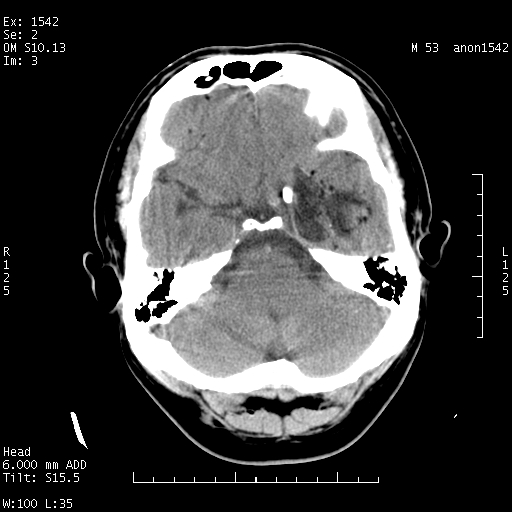

标题: CT10811:M53Y,头痛一月.其它没有什么 [打印本页]

左侧鞍旁不规则低密度,此区域和侧脑室有液平。若无外伤史。考虑左侧鞍旁表皮样囊肿自发破溃。

鞍旁颞叶低密度灶.其中散在空气影.还有侧脑室.是否考虑脑脓肿(请提供病史情况)

1.支持考虑左侧鞍旁表皮样囊肿自发破可能;

有肿瘤样病变破溃,沿外侧裂生长,为什么不考虑胆脂瘤?

1 囊性肿物. 2 请楼主上传介少病人资料. 3 表皮样囊肿或胆脂瘤都在考虑范围内,确切的不知ct值是多少.4了解病史后在缺定.